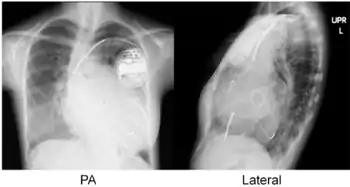

- Atrial lead at the right appendage

- Right ventricular lead at the apex

- Left ventricular lead through the coronary sinus.[7]